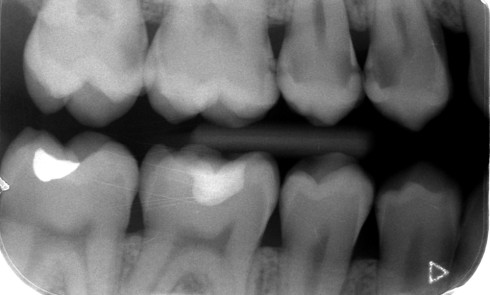

De nombreuses enquêtes de pratique ont montré la variation des décisions diagnostiques et thérapeutiques en cariologie d’un pays à l’autre...Troubles du sommeil et douleurs orofaciales chroniques : un modèle d’interaction